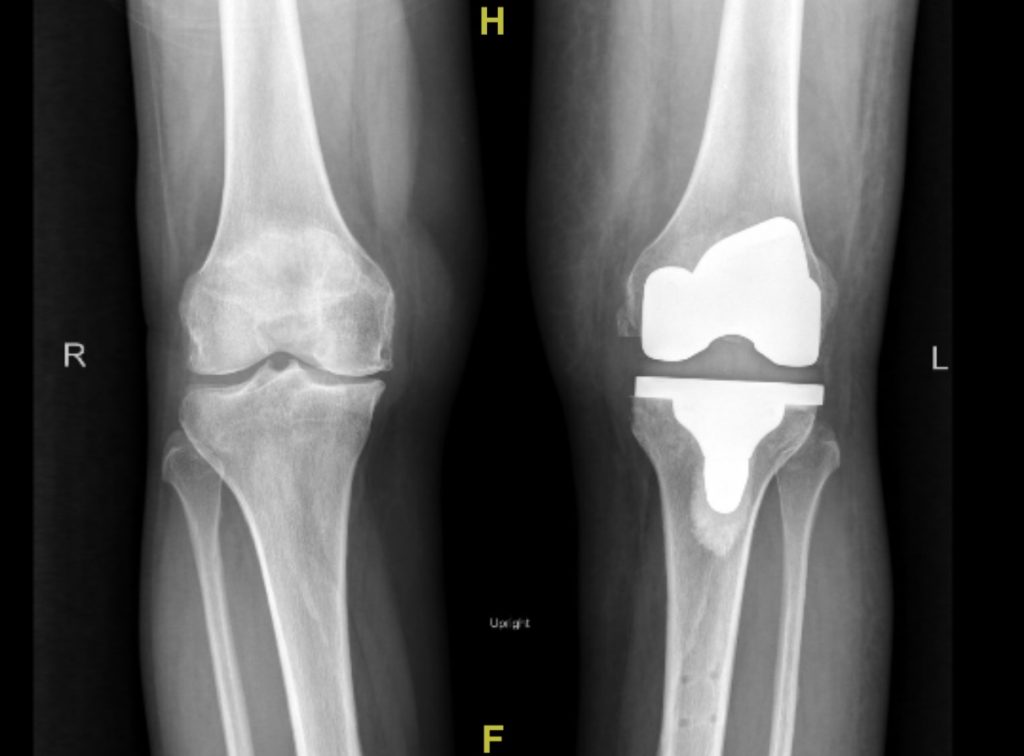

Robotic Technology For Knee Replacement . Robotic orthopedic surgery can help align artificial joint components more precisely for partial knee and total hip replacements. There are several different robotic platforms that can be used for knee replacement surgery, and each one is a bit different. This model helps the surgeon to plan the operation with greater accuracy, taking into account the unique anatomical features and alignment needs of the patient’s knee. Using computed tomography (ct) scans, a virtual model of a patient’s knee. Meet rosa, a robotic surgical assistant, developed by zimmer biomet. Robotic technology is increasingly used for knee replacement surgery and is favoured over traditional surgery among some surgeons. Robotic knee replacement uses advanced imaging and computer modelling to generate a detailed 3d map of the knee. The rosa knee system’s precision robotic arm helps increase the success of your knee replacement surgery (compared. A major national study will pitch human skill against machine precision as it.